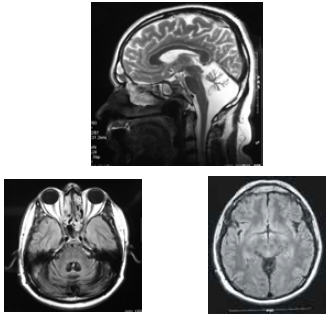

José, com 42 anos de idade, foi renovar sua carteira de motorista e, ainda na entrada do consultório, o médico observou uma marcha com base alargada e insegura. Durante a avaliação clínica, ao testar a coordenação, o médico verificou tremor de intenção à prova índex-nariz, dismetria e disdiacocinesia bilateral. Os pares cranianos, a força muscular e os reflexos — profundos e superficiais — eram normais. A fala de José era pausada, silabada. Ao ser questionado sobre o uso de álcool, negou-o e referiu que o problema do desequilíbrio vem piorando nos últimos dez anos, fato que provocou o acompanhamento médico e motivou a realização de uma ressonância nuclear magnética (RNM), cujas imagens são apresentadas abaixo.

Acerca desse quadro clínico, julgue o seguinte item.

Das causas metabólicas que podem causar sintomas semelhantes, está a deficiência de vitamina E.